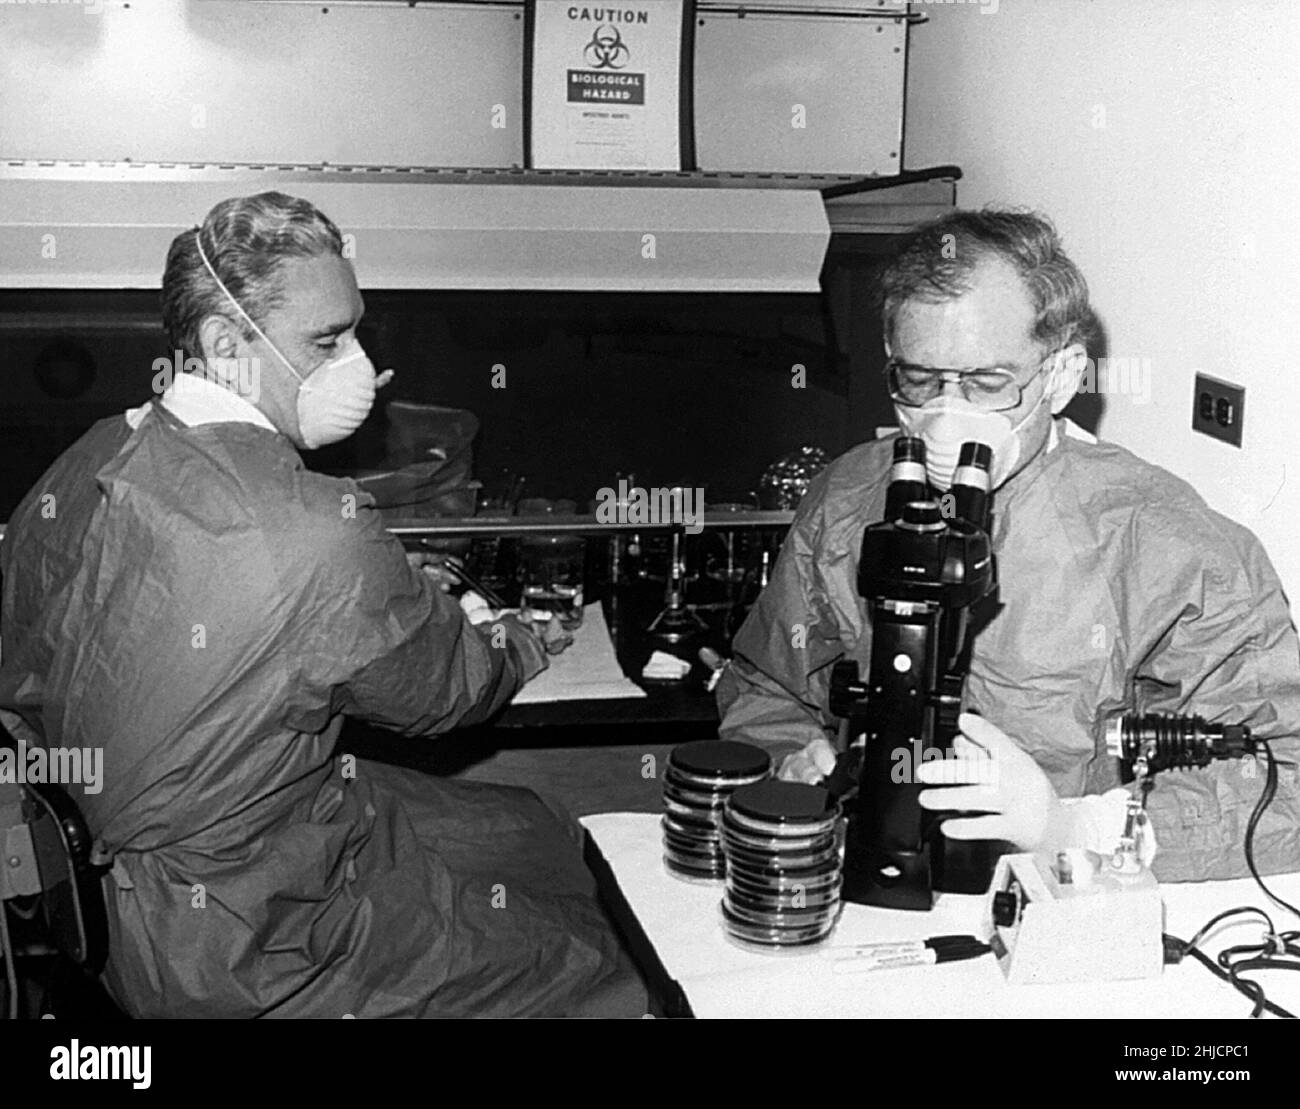

Dieses Bild aus dem Jahr 1977 zeigt die Mikrobiologen Joseph E. McDade (links) und Charles C. Shepard (rechts), die den Erreger isolieren, der den Ausbruch der Legionäre 1976 auf einer Tagung der American Legion in Philadelphia verursacht hatte. Sie stellten fest, dass die Ursache eine Art von Bakterien war, die sie Legionella pneumophila nannten. Stockfotohttps://www.alamy.de/image-license-details/?v=1https://www.alamy.de/dieses-bild-aus-dem-jahr-1977-zeigt-die-mikrobiologen-joseph-e-mcdade-links-und-charles-c-shepard-rechts-die-den-erreger-isolieren-der-den-ausbruch-der-legionare-1976-auf-einer-tagung-der-american-legion-in-philadelphia-verursacht-hatte-sie-stellten-fest-dass-die-ursache-eine-art-von-bakterien-war-die-sie-legionella-pneumophila-nannten-image458814420.html

Dieses Bild aus dem Jahr 1977 zeigt die Mikrobiologen Joseph E. McDade (links) und Charles C. Shepard (rechts), die den Erreger isolieren, der den Ausbruch der Legionäre 1976 auf einer Tagung der American Legion in Philadelphia verursacht hatte. Sie stellten fest, dass die Ursache eine Art von Bakterien war, die sie Legionella pneumophila nannten. Stockfotohttps://www.alamy.de/image-license-details/?v=1https://www.alamy.de/dieses-bild-aus-dem-jahr-1977-zeigt-die-mikrobiologen-joseph-e-mcdade-links-und-charles-c-shepard-rechts-die-den-erreger-isolieren-der-den-ausbruch-der-legionare-1976-auf-einer-tagung-der-american-legion-in-philadelphia-verursacht-hatte-sie-stellten-fest-dass-die-ursache-eine-art-von-bakterien-war-die-sie-legionella-pneumophila-nannten-image458814420.htmlRM2HJCPD8–Dieses Bild aus dem Jahr 1977 zeigt die Mikrobiologen Joseph E. McDade (links) und Charles C. Shepard (rechts), die den Erreger isolieren, der den Ausbruch der Legionäre 1976 auf einer Tagung der American Legion in Philadelphia verursacht hatte. Sie stellten fest, dass die Ursache eine Art von Bakterien war, die sie Legionella pneumophila nannten.